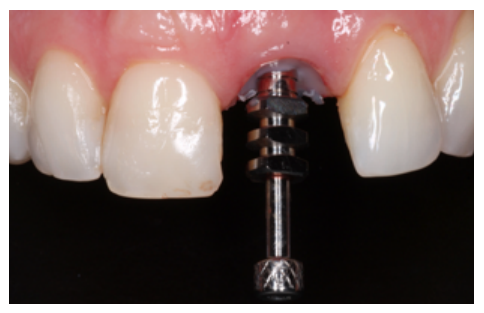

Primary stability was obtained, achieving anchorage in the palatal residual bone at an insertion torque of 35 N/ cm2 . Subsequently, a temporary prosthetic abutment was placed.

Provisional prosthetic phase

Before starting the provisional screw-retained restoration on the OII, the correct position of the abutment in terms of the provisional prosthesis was verified. The abutment was relined with the provisional through the use of flowable composite (Figures 8 and 9).